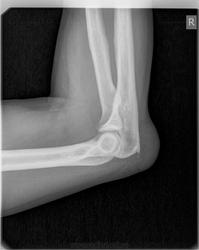

шпора olecranon

причем в обоих суставах.

+ бурсит обоих суставов

Подагры нет?

Есть.

Вот я так и увидела.

Хорошее дело цифра! Такие тофусы на плёнке не будут столь наглядными. Для учебника просто красота!

Снимки сделаны на платной основе. В направлении ортопеда- локтевые суставы в боковых проекциях. Как предложить больше?